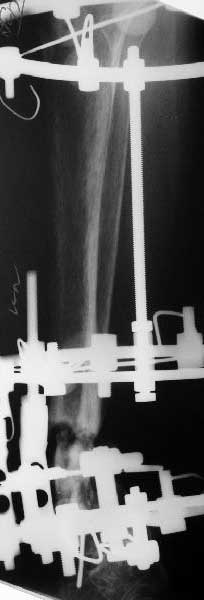

В общем, начали c аппарата - нложили, малоберцовую внизу пересекли, выбрали люфт, раз дальше сопротивление пошло - выведем постепенно.

Картинки приложены. Жду комментариев.

e> Какова была подвижность в зоне несращения после остеотомии малоберцовой

e> кости?

Примерно такова, как было на снимках в аппарате. Все, что относительно свободно было, выбрали, а дальше уже было тугое сопротивление тканей.

e> Была ли возможность одномоментной коррекции оси б.б кости и если да,

e> то почему не штифтование, а аппарат?

Аппарат - чтобы плавно исправить ось. В приложении - снимки на момент окончания коррекции в аппарате, фото с операции, и послеоперационная рентгенограмма.